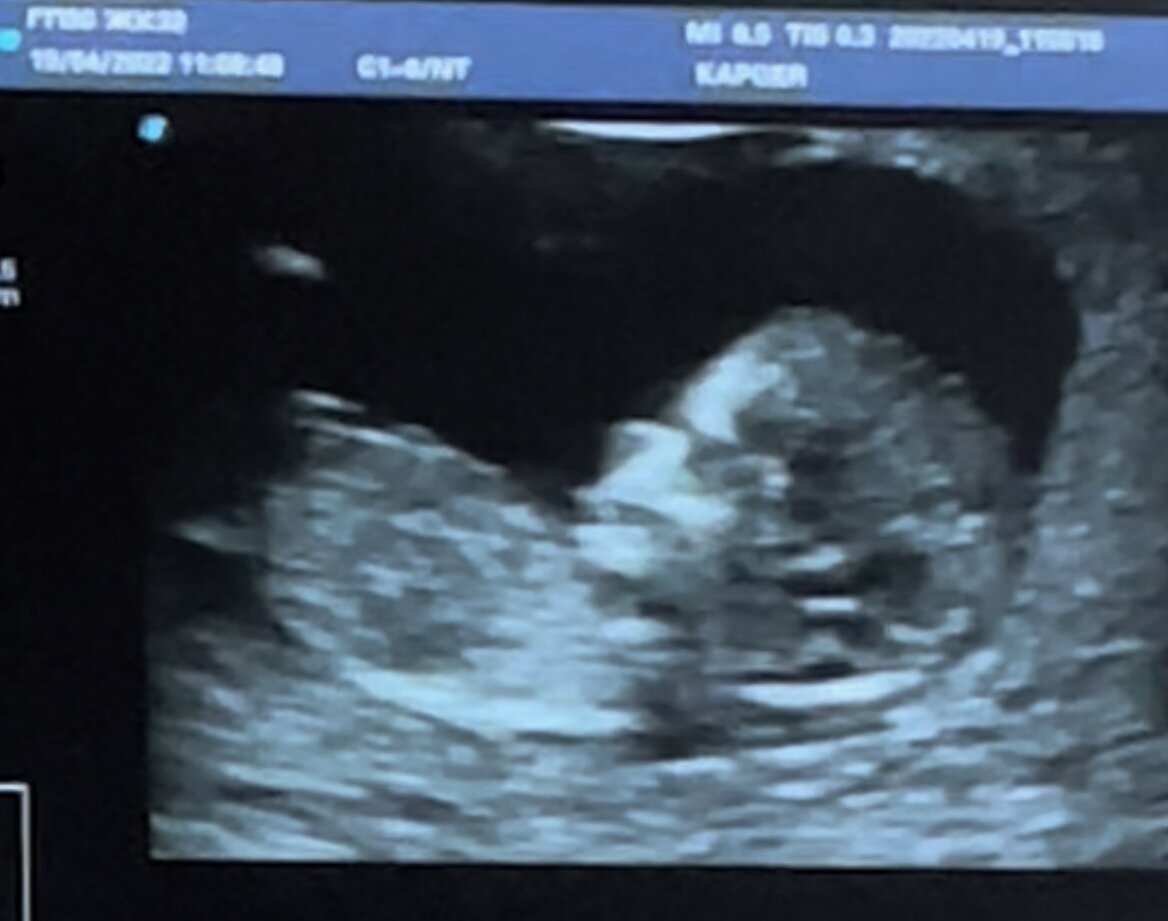

И вот пошли первые знакомства с нашим ребенком.

Вот и наш малыш.

Дело было летом. В июне. Это наш первый скрининг. Почему то его все называют УЗИ, и мне так понятнее, но это СКРИНИНГ (видео я скину отдельно). Запомните, мужики!

Был ли я счастлив когда увидел малыша? Да вообще. Опять начало в душе увеличиваться такое качество как ответственность. Прописали таблетки, витамины и домой.